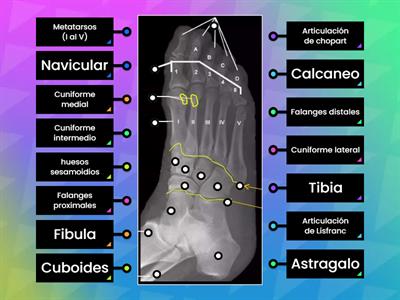

rx pie oblicuo

Označený diagram